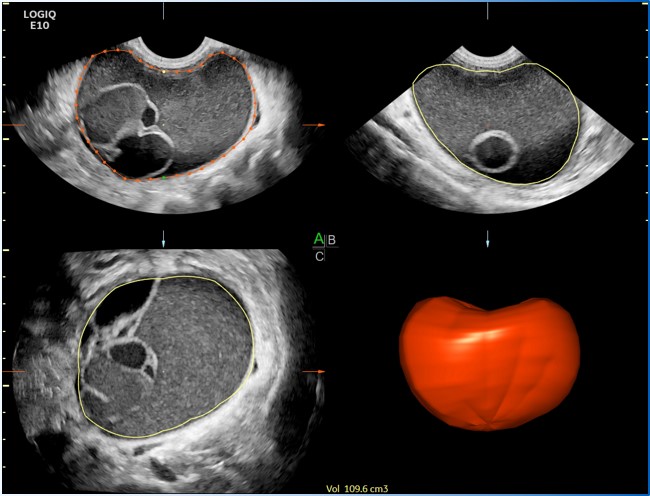

查看完整图像 查看完整图像 Ecograf multidiscipline de înaltă performanță, vârful de gamă pentru familia Logiq Furnizor: 通用电气医疗集团 Categorie: Ultrasonografie 水平制表符 Descriere Sistemul de ecografie Logiq E10 reprezintăvarful de gamăal sistemelor multidisciplinare din伽马Logiq, ingloband pe朗ătehnologii构造deție de ultimă属țieș我德opțiuni软件保健il fac溶解ția potrivităpentru oricare dintre aplicațiile clinice:腹部,血管,părți moi,心脏科,obstetrică și ginecologie,泌尿科,新生儿科,儿科și transraniene等。 Configurația标准铜锭și: Optimizare automată - auto-optimizarea imaginii în module 2D, color și Doppler, cu atingerea unui singur button Componentă CrossXBeam -复合分辨率成像- tehnică de compunere spațială a imaginii, SRI-HD,斑点减少成像,虚拟凸și彩色流量化 Bază de date cu informaţii despre pacienţi 逻辑视图-想象空间的消失的可能性 b -流模块pentru vizualizare în cele mai bune condiții ale vascularizației țesuturilor 应变弹性模数-应变弹性模数包括și part de cuantificare și analiză。 自动IMT测量- măsurare automată a grosimi intimei媒体的可能性 Pachete și opțiuni specializpentru analiză și ghidare a umitor protococum: Scan Assistant, Compare Assistant, Thyroid Productivity Package, Measure Assist Breast, Breast Productivity Package și Measure Assistant OB e lângă multitudinea de technologii incluse în configurația standard, echipamentul permite și upgrade-uri ulterioare cu technologii avansate precum: 模块pentru vizualizare și analiză a imaginilor cu agent de contrast: Coded contrast Imaging cu opțiunea Parametric Imaging Pachet de măsurători și analiză avansată pentru aplicații de cardiologie precum:心脏AFI și压力回声 Realtime 4D cu opțiunile: VOCAL II Volume Calculation, VCI Static (Volume Contrast Imaging), TUI - Tomographic超声成像,OmniView, STIC, pentru achiziție, manipulare și analiză a volumelor 剪切波弹性成像-尖端剪切波弹性模数 DVR,强制凝胶加热,无线局域网,连续波多普勒 权力的助理 Imagini clinice 查看完整图像 查看完整图像 查看完整图像 查看完整图像 查看完整图像 查看完整图像 查看完整图像 查看完整图像 Descarcă Descarcă: 兄弟șurăLogiq E10 Broșură Logiq E10 cardiologie Broșură Logiq E10 întretinere Broșură Logiq E10干预 Broșură Logiq E10放射科 Broșură Logiq E10 musculoscheletal Broșură Logiq E10小儿科 Educatie 平台LogiqClub a fost dezvoltată pentru a susține educația continuă a utilzatorilor de sisteme de ecografie Logiq și pentru a pune la dispoziția acestora cele mai noi informații despre produse, ghiduri de practică medicală,文章și mai ales pentru a încuraja schimbul de experieță și de a răspunde tuturor întrebărilor utilzatorilor care folosesc ecografele Logiq。 Cu înregistrare simplă LogiqClub depășește barierele de timp și spațiu și unește utilzatorii de ecografe Logiq pentru un act medical la cele mai înalte standard。 Link-ul de inregistrare:https://www.logiqclub.net/emea/home 视频 GE医疗保健的新功能- LOGIQ™E10 GE医疗保健新产品LOGIQ™E10的视频 Voluson E10 BT18 Voluson E10 BT18视频 Specialitati: ATI Cardiologie Chirurgie一般ă Endocrinologie Gastroenterologie 药物de家庭 药物de Urgenta 药物Interna Nefrologie Neonatologie Obstetrica——Ginecologie Radiologie - Imagistică medicală Recuperare Medicala Reumatologie